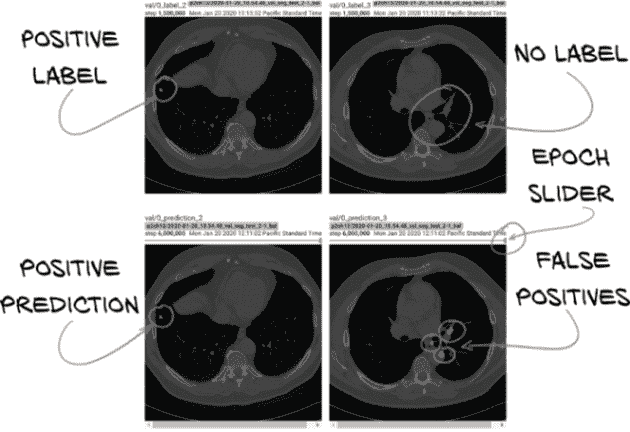

我们没有一种单一正确的方式来构建我们的图像记录。我们将从训练集和验证集中各选取几个 CT 图像。对于每个 CT 图像,我们将选择 6 个均匀间隔的切片,端到端显示地面真实和我们模型的输出。我们之所以选择 6 个切片,仅仅是因为 TensorBoard 每次会显示 12 张图像,我们可以将浏览器窗口排列成一行标签图像在模型输出上方。以这种方式排列事物使得我们可以轻松地进行视觉比较,正如我们在图 13.16 中所看到的。

图 13.16 顶部行:训练的标签数据。底部行:分割模型的输出。

还请注意prediction图像上的小滑块点。该滑块将允许我们查看具有相同标签的先前版本的图像(例如 val/0_prediction_3,但在较早的时期)。当我们尝试调试某些内容或进行调整以实现特定结果时,能够查看我们的分割输出随时间变化的情况是有用的。随着训练的进行,TensorBoard 将限制从滑块中可查看的图像数量为 10,可能是为了避免用大量图像淹没浏览器。

一旦我们有了prediction_a,我们需要构建一个image_a来保存 RGB 值以供显示。我们使用np.float32值,需要在 0 到 1 的范围内。我们的方法会通过将各种图像和掩模相加,使数据在 0 到 2 的范围内,然后将整个数组乘以 0.5 将其恢复到正确的范围内。

列表 13.29 training.py:346, .logImages

ct_t[:-1,:,:] /= 2000

ct_t[:-1,:,:] += 0.5

ctSlice_a = ct_t[dl.dataset.contextSlices_count].numpy()

image_a = np.zeros((512, 512, 3), dtype=np.float32)

image_a[:,:,:] = ctSlice_a.reshape((512,512,1)) # ❶

image_a[:,:,0] += prediction_a & (1 - label_a)

image_a[:,:,0] += (1 - prediction_a) & label_a # ❷

image_a[:,:,1] += ((1 - prediction_a) & label_a) * 0.5 # ❸

image_a[:,:,1] += prediction_a & label_a # ❹

image_a *= 0.5

image_a.clip(0, 1, image_a)

❶ 将 CT 强度分配给所有 RGB 通道,以提供灰度基础图像。

❷ 假阳性标记为红色,并叠加在图像上。

❸ 假阴性标记为橙色。

❹ 真阳性标记为绿色。

我们的目标是在半强度的灰度 CT 上叠加预测的结节(或更正确地说,结节候选)像素以各种颜色显示。我们将使用红色表示所有不正确的像素(假阳性和假阴性)。这主要是假阳性,我们不太关心(因为我们专注于召回率)。1 - label_a反转标签,乘以prediction_a给出我们只有预测像素不在候选结节中的像素。假阴性得到添加到绿色的半强度掩模,这意味着它们将显示为橙色(1.0 红和 0.5 绿在 RGB 中呈橙色)。每个正确预测的结节内像素都设置为绿色;因为我们正确预测了这些像素,不会添加红色,因此它们将呈现为纯绿色。

然后,我们将数据重新归一化到0...1范围并夹紧它(以防我们在这里开始显示增强数据,当噪声超出我们预期的 CT 范围时会导致斑点)。最后一步是将数据保存到 TensorBoard。